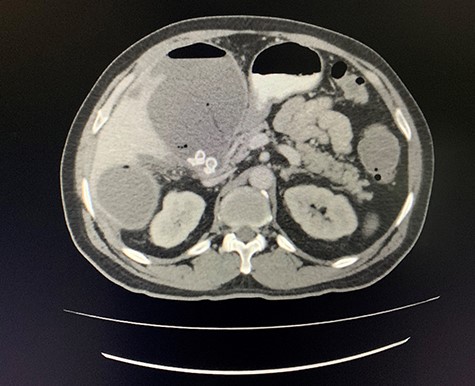

A computed tomography (CT) scan of the abdomen revealed an enlarged, thickened gallbladder with multiple stones, communicating with an intrahepatic collection in segment 4 measuring 116 × 80 mm, with an associated air fluid level and air locules (Fig. 1). There was an apparent fistulous tract to the hepatic flexure of the colon, another large collection in segment 6 (97 × 96 mm) as well as other smaller collections (Figs 2 and 3).

Axial view of CT scan of the abdomen with oral contrast demonstrating enlarged, thickened gallbladder with radio-opaque gallstones. Two large liver abscesses in segment 4 measuring 116 × 80 mm (communicating with the gallbladder) and segment 6 measuring 97 × 96 mm with air locules noted.